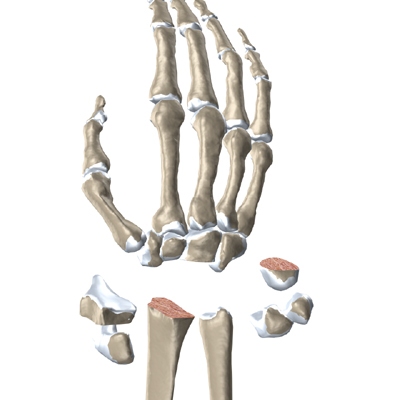

The wrist is made up of eight separate small bones, called the carpal bones. The carpal bones connect the two bones of the forearm, the radius and the ulna, to the bones of the hand. The metacarpal bones are the long bones that lie mostly underneath the palm. The metacarpals are in turn attached to the phalanges (the bones in the fingers and thumb).

Modern artificial wrist joints are made of metal and plastic. The part that fits against the end of the radius bone of the forearm is called the radial component. It is made up of two pieces. A flat metal piece is placed on the front part of the radius. It has a stem that attaches down into the canal of the bone. A plastic cup fits onto the metal piece, forming a socket for the artificial wrist joint.

The part that replaces the small wrist bones is called the distal component. This piece is made completely of metal. It is globe shaped to fit into the plastic socket on the end of the radius. The metal distal component is attached by two metal stems that fit into the hollow bone marrow cavities of the carpal and metacarpal bones of the hand.

The plastic used in artificial joints is tough and slick. It allows the two pieces of the new joint to glide easily against each other as you move your wrist. The ball and socket allow movement of the wrist in all directions.